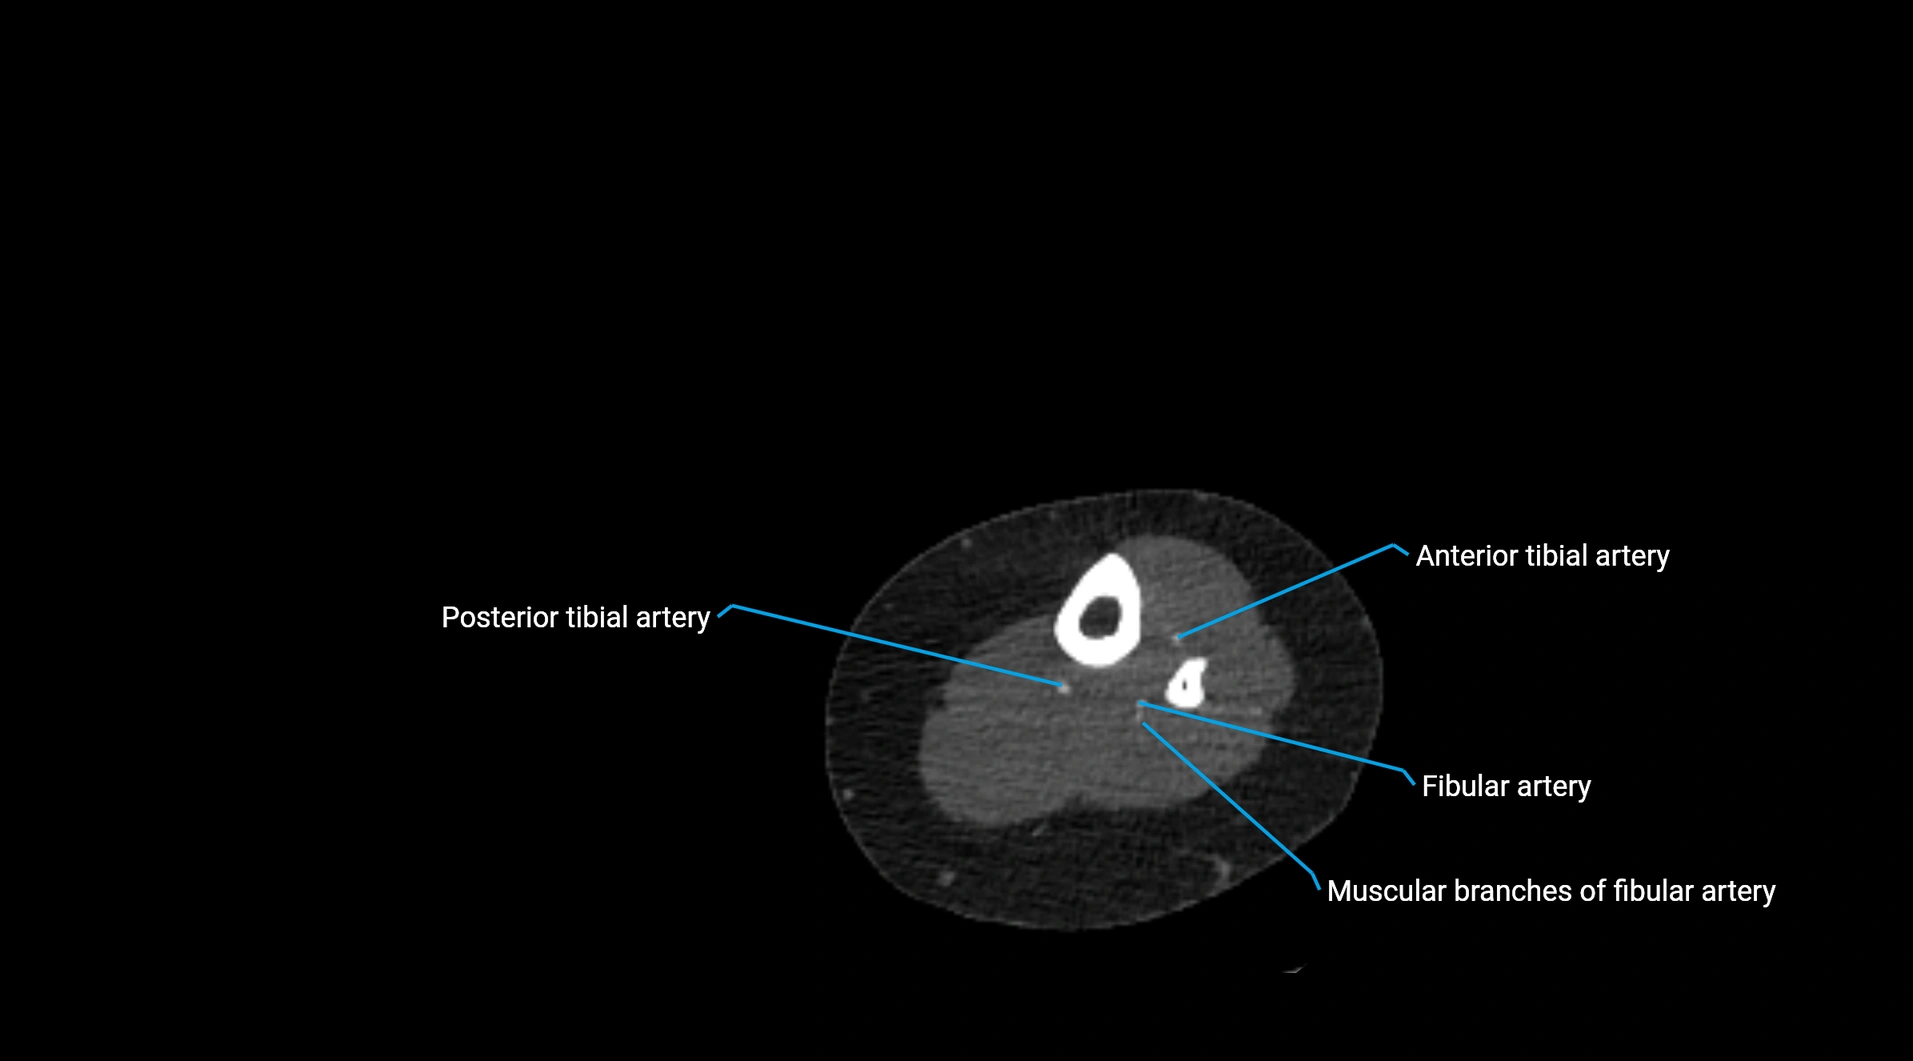

CT images

image

Contrast-enhanced CT (CTA):

• Gold standard for abdominal aortic imaging

• Provides excellent detail of lumen, wall, aneurysm, thrombus, and branch vessels

• Multiplanar and 3D reconstructions help in aneurysm measurement, stent graft planning, and dissection evaluation